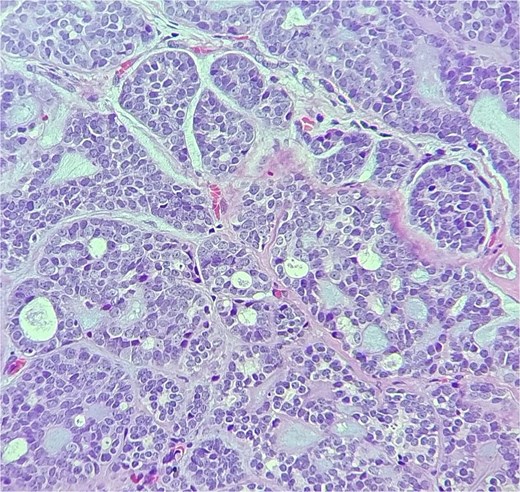

She was kept on follow-up for four years with clinical exams and MR imaging until she felt a palpable mass at the left lower dental root with local disease recurrence on orbit MRI (Fig. 3). An excisional biopsy from the submandibular mass revealed ACC, indicating metastatic disease. She was consequently given five cycles of paclitaxel and carboplatin chemotherapy.

Orbit MRI showed lobulated well-defined lesion, hyperintense to intermediate on T2W (a), hypointense on T1W (b) structures with cystic changes measuring 2 × 1.5 cm and 2 × 1.2 cm. After IV contrast administration they showed heterogeneous moderate enhancement.